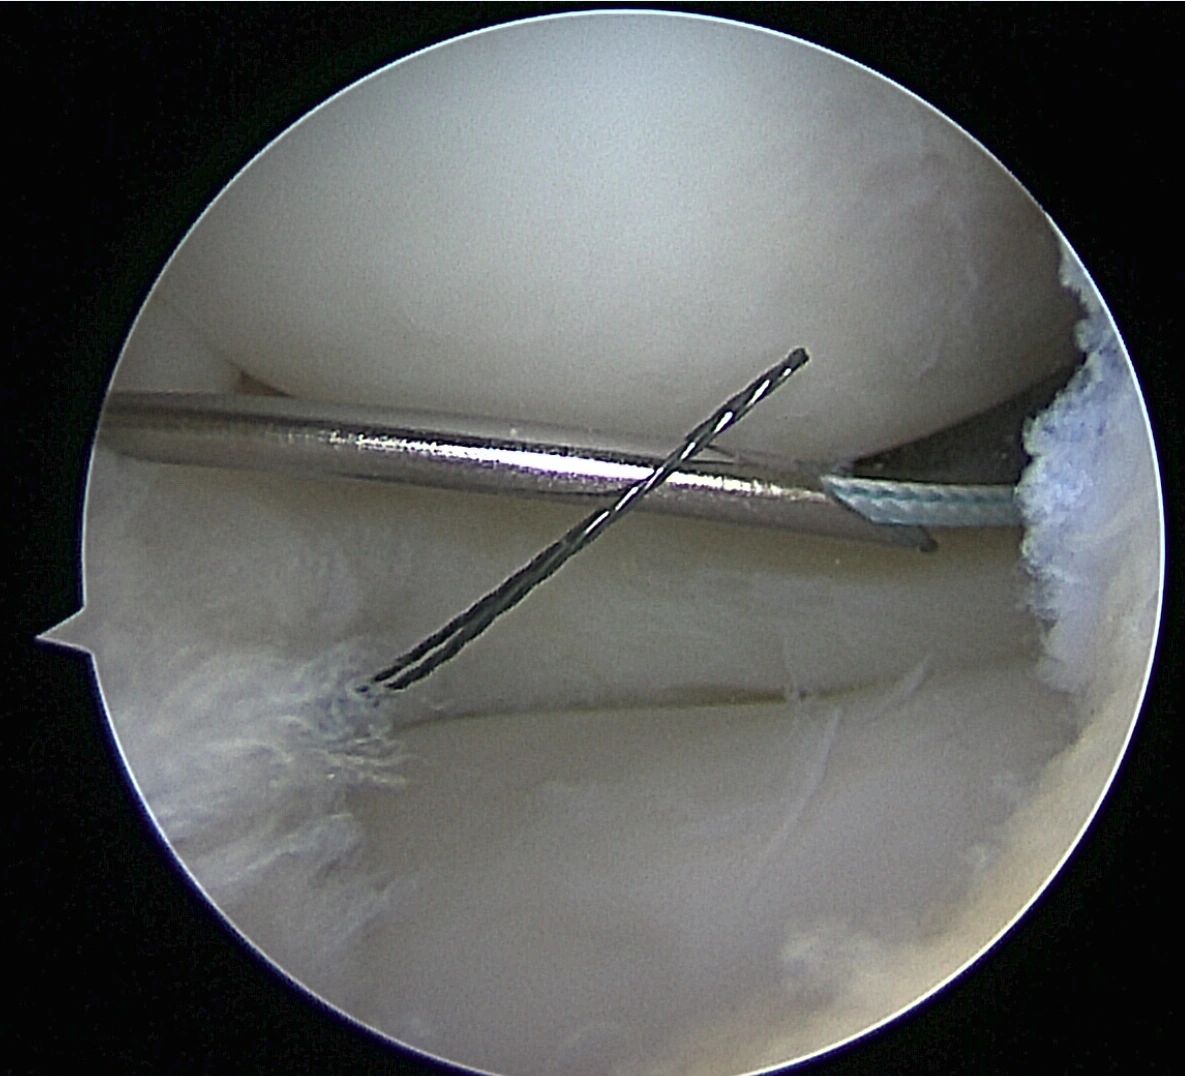

- Meniscus Surgery

- Meniscus Surgery 2